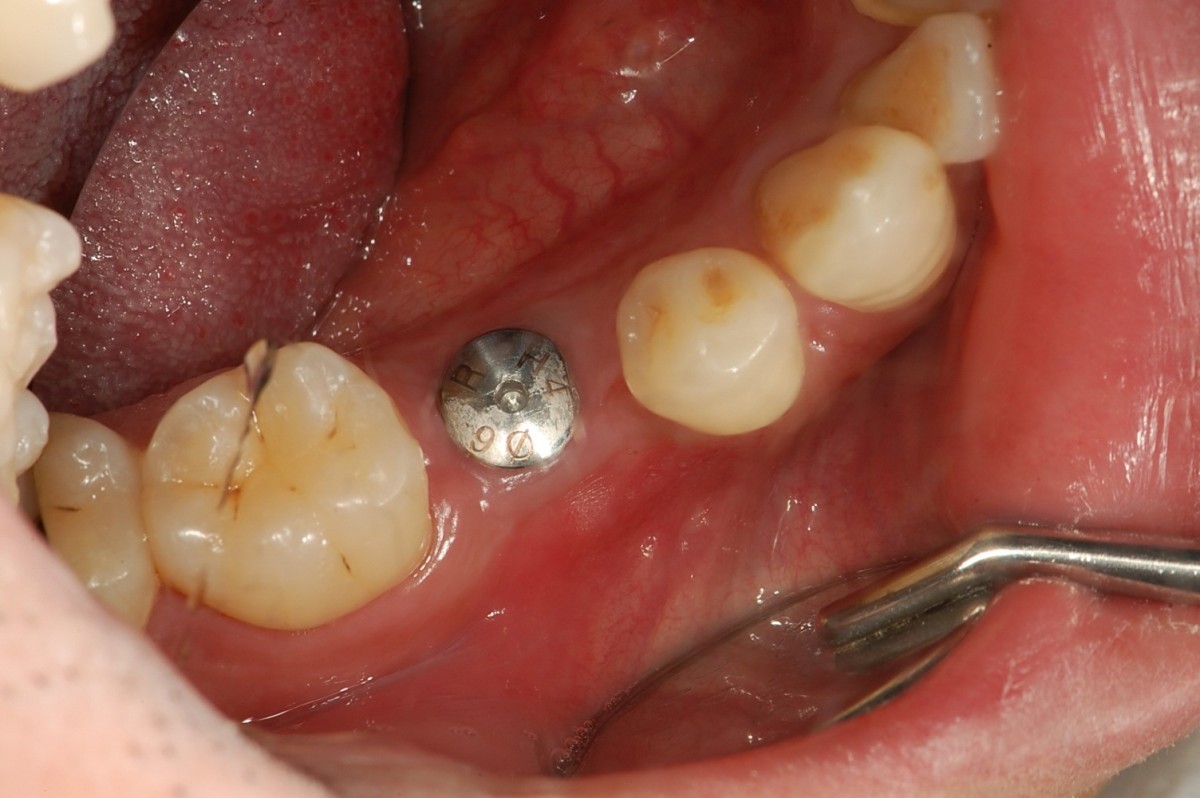

▲8 years after restoration.